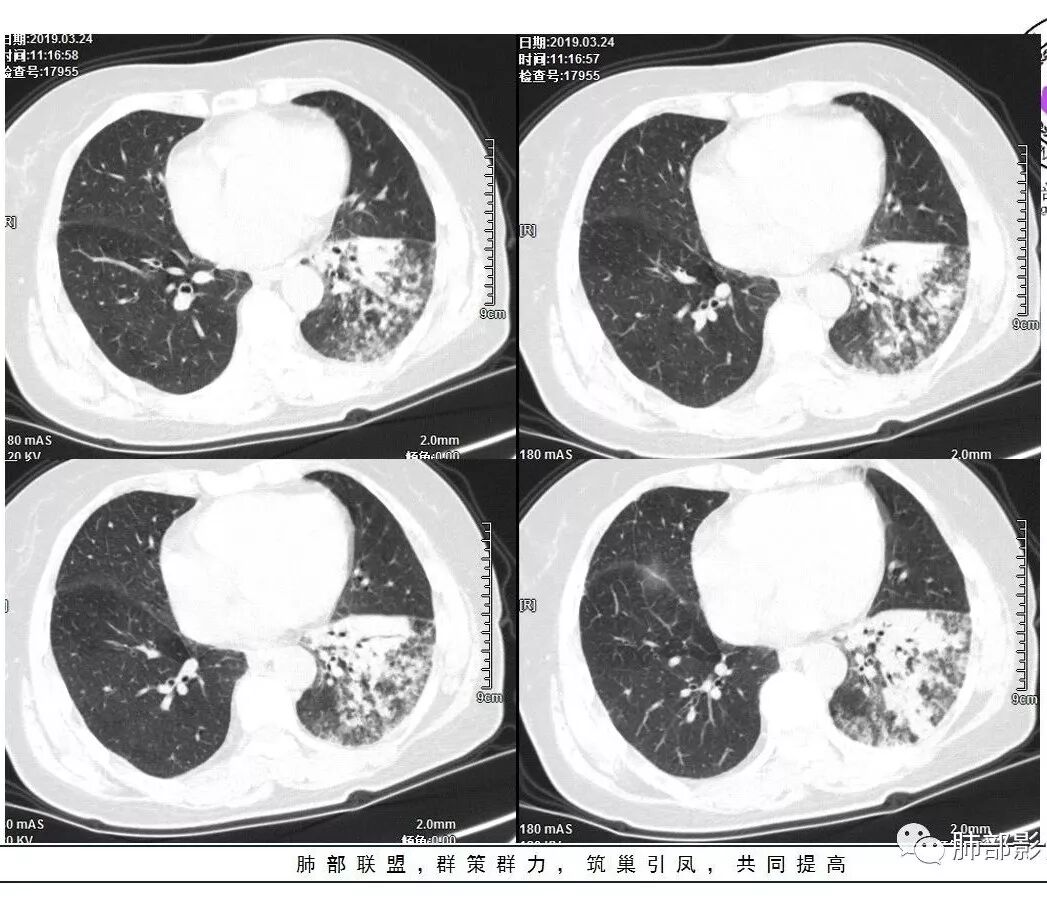

胸CT:左下叶基底段支气管狭窄,沿支气管分布斑片实变影、网格影、磨玻璃影,支气管充气征,无重力效应,左肺门淋巴结肿大、钙化。

左下叶实变影及磨玻璃影,内部支气管扩张、僵直。纵膈肺门淋巴结钙化。balf结核杆菌核酸阳性。

左肺下叶背段斑片影,部分病灶实变,支气管束分布,爬行征,部分支气管狭窄,内蜂窝状坏死。叶间裂阻挡,膨隆。增强见血管影。肺门淋巴结增大。结合临床,抗感染治疗无效,间断低热,结核阳性。考虑结核合并肺炎型肺癌(腺癌)。

老年男性,咳嗽气短2月,发热2天,左肺下叶大片磨玻璃实变影,实变区支气管进入,有的穿过,有的阻塞,走形有扭曲,有小厚壁空洞,磨玻璃影边界有的清楚,有的模糊,周围有小腺泡结节影,病灶整体感觉沿支气管树分布,病灶有多形态,多灶性特点,双肺门淋巴结钙化,左肺门淋巴结肿大,虽然病灶有明显强化,我还是考虑感染,肺结核可能性大,不排除合并肺癌可能。

这是老问题:1、肺门区软组织密度影较弥漫;我们常规鉴别的就是结核?鳞癌?既往我们群里基本这两方向。2、弥漫的淋巴结钙化,加上马赛克灌注。马赛克灌注的原因是两个,一个是肺动脉的,一个就是小气道的问题。我们看增强的区域,没有看到栓塞,所以我倾向于小气道的问题,就是弥漫气道病变,慢性气道病变要考虑。我怀疑有没有淀粉样变性累及气道壁改变的可能。淀粉样变性是一个继发性病变,结核也可以,粉尘也可以。

这个病例支气管狭窄后扩张,肺门区有很多钙化的淋巴结,两肺弥漫的马赛克灌注,肺门淋巴结这么多,一个结核,一个尘肺,然后就是一个淀粉样变性,这几种最常见。鳞癌因为老年女性,除非吸烟,不太考虑,又不能绝对排除,所以就把鳞癌放到后。

今天这个病例有个明显的支气管狭窄,我倾向炎性,主要是和钙化淋巴结相关的,可能是继发的淀粉样变性。到底是什么感染,结核还是其他。我想看看复查后这个淋巴结,有没有突入到支气管腔内,如果有,他是继发于炎症的(比如中叶综合征,就是周围淋巴结压迫支气管,因为钙化淋巴结比较硬,支气管壁扛不住压力,突入支气管腔内,导致管腔狭窄,我们也称为结石征),如果没有,就和淋巴结关系不密切。之前有一例淀粉样变性的,淋巴结弥漫钙化,一种罕见的浆细胞型的CD。